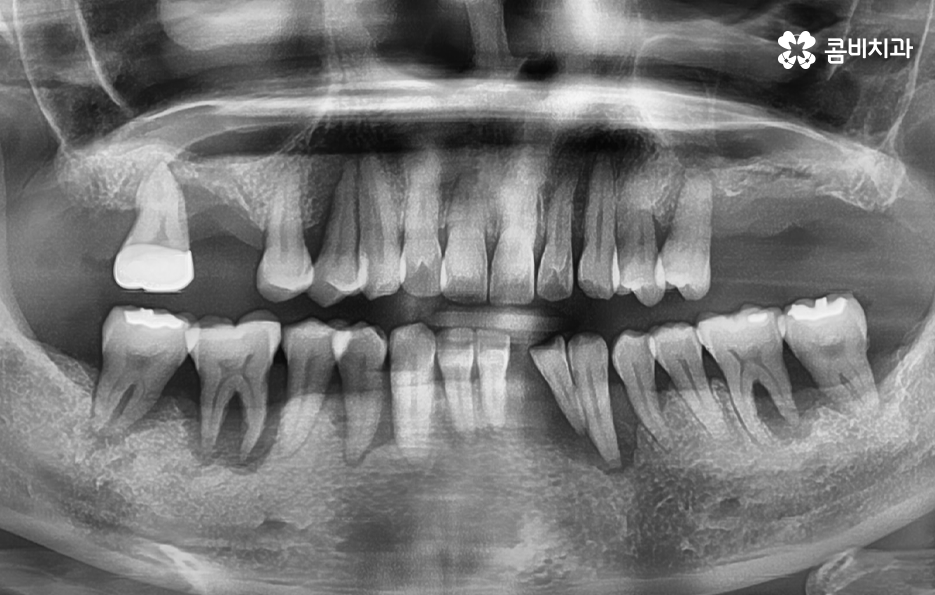

우리가 어릴 때 주로 발생되는 충치의 형태는 치아의 씹는 면에서 충치가 시작되어 점점 깊어지는 경우가 많았다면 성인 이후에는 충치의 발생률 자체는 줄어들지만 치아 옆면 충치 즉 치아와 치아가 맞닿는 부분의 인접면 충치로 인해 치아에 큰치료를 해야 하는 상황이 종종 발생되고 있는데요. 치아 옆면 충치 뿐 아니라 잇몸이 내려앉고 염증이 발생되는 치주질환은 구강 내 세균관리가 잘 안되어서 발생되는 구강내 대표적 질환이자 중년이후에 많은 분들이 놓치고 있는 문제라는 점에서 제대로 알아둘수록 자연치아 뿐 아니라 소중한 잇몸 건강에도 큰 도움이 될 거예요

치아 옆면 충치의 경우 사실 더 큰 문제가 될 수 있는 점은 발견 자체가 늦어지는 경우가 많고 눈에도 잘 띄지 않기 때문에 환자분께서 검진을 미루고 다소 시리거나 아파도 참고 지내다 보면 치아의 옆부분에서 충치가 시작되었기 때문에 치아의 신경조직까지 손상되기에 쉬운 위치라는 점에서도 신경치료로 이어지는 경우도 흔하게 발생되고 있어요

우선 치아로 따지자면 치아의 씹는 면에 발생된 충치는 치료도 비교적 쉬운 편이고 치아의 구조로 볼 때도 치아의 윗 부분은 법랑질이 신경과의 거리가 어느정도 있기 때문에 충치가 몇번 치료해도 레진이나 인레이 정도로 치료가 끝낼 수 있는 경우가 많은데 치아 옆면 충치의 경우에는 치아 사이에 하루 이틀 음식물이나 이물질이 낀 것이 아니라 오랜 시간 동안 지속적으로 치실 사용이나 스케일링을 잘 안한 경우에 주로 발생되기 때문에 단순히 어금니 혹은 사랑니 주변에만 발생되는 것이 아니라 치아의 여러 부분에서 치아 옆면 충치가 동시에 발생되는 경우가 있는데요

치아 옆면 충치는 치아와 치아 사이에 맞닿는 부분에 발생하기 때문에 최소 2개의 치아에서 발생되는 경우가 일반적이며 습관적인 부분이 원인이 되기 때문에 치과 치료가 늦어지면 여러 치아에서 동시에 발생되는 경우도 자주 볼 수 있기 때문에 치아 수명을 급격히 저하시키는 원인이 되고 있어요